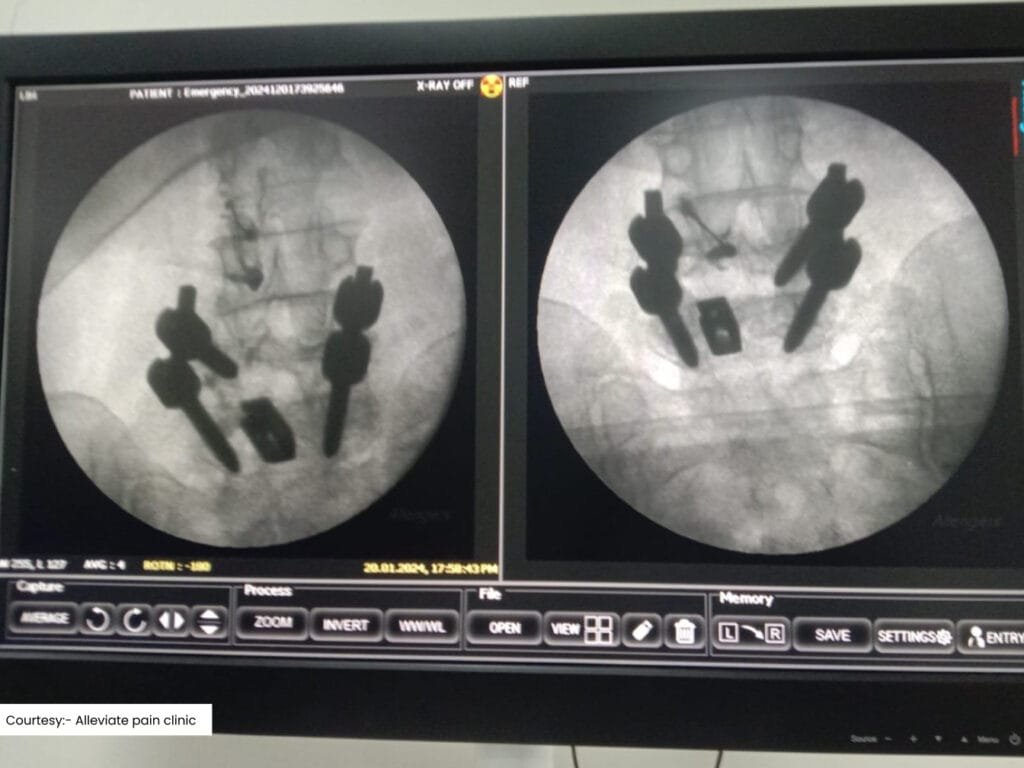

Scan 2

Platelet Rich Plasma Injection of the Sacroilac joint done under fluoroscopy:,

PRP therapy involves injecting a concentration of the patient’s own platelets into the affected area. The growth factors in PRP promote tissue repair and regeneration, making it particularly effective for treating SI joint dysfunction and facet joint arthritis.